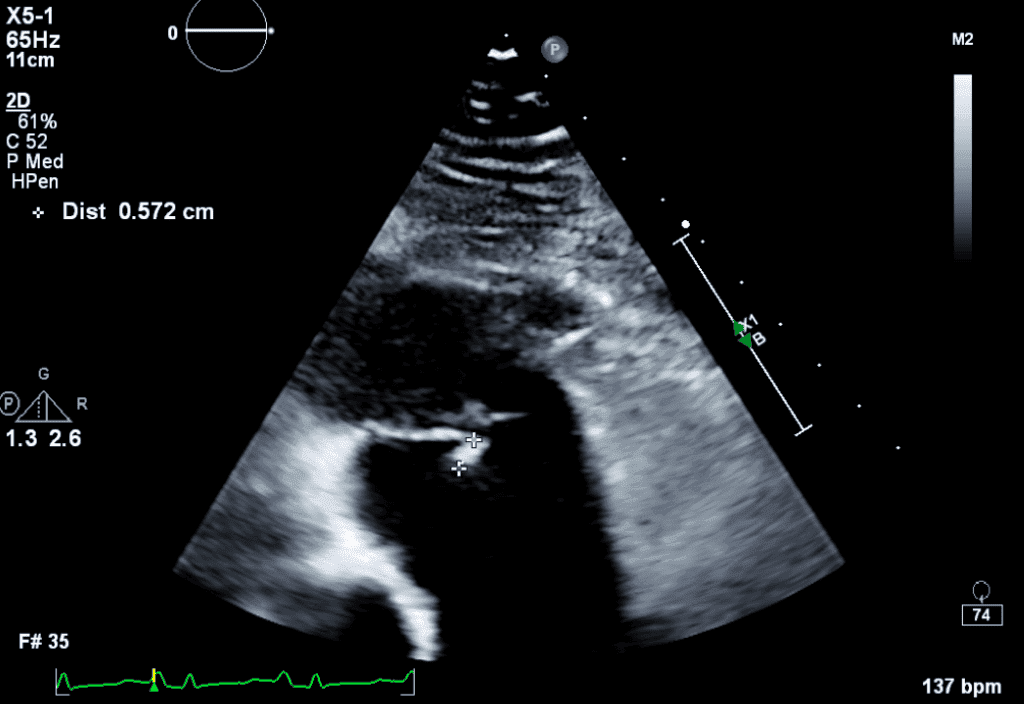

This course on Infective Endocarditis explores the role of echocardiography in diagnosing and managing the condition. Learn about different diagnostic techniques, including transthoracic and transesophageal echocardiography, and gain insights into pathophysiology, clinical presentation, treatment options, and complications.

Accurately identify and interpret echocardiographic findings indicative of endocarditis in both native and prosthetic valves.

Implement an effective approach to distinguish infective endocarditis from other cardiac conditions, enabling timely and appropriate management.

Utilize echocardiography as a valuable tool for assessing treatment response, monitoring complications, and guiding surgical interventions in complicated endocarditis cases.